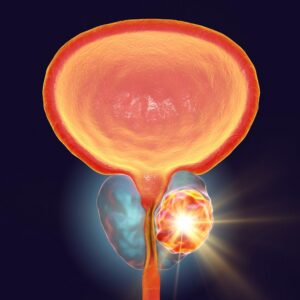

Ο καρκίνος του προστάτη είναι μια συχνή μορφή καρκίνου στους άνδρες, που αναπτύσσεται στον προστάτη, έναν μικρό αδένα του ανδρικού αναπαραγωγικού συστήματος. Ο προστάτης βρίσκεται κάτω από την ουροδόχο κύστη και περιβάλλει την ουρήθρα. Η λειτουργία του προστάτη έχει σχέση με τη γονιμότητα.

Καρκίνος του προστάτη: Χειρουργική αντιμετώπιση

Η ριζική προστατεκτομή αποτελεί τη θεραπεία εκλογής για την αντιμετώπιση του τοπικά εντοπισμένου καρκίνου του προστάτη. Η ρομποτική ριζική προστατεκτομή είναι πλέον το gold standard, καθώς ήρθε να καλύψει τα κενά της ανοιχτής και κυρίως της λαπαροσκοπικής προστατεκτομής, τα οποία ήταν μεταξύ άλλων, η σχετική ακαμψία των λαπαροσκοπικών εργαλείων περιορίζοντας την ελευθερία κινήσεων και κατά συνέπεια την εκτέλεση των χειρουργικών χειρισμών, και η δυσδιάστατη εικόνα.

Οφέλη της ρομποτικής ριζικής προστατεκτομής

Για τη συντριπτική πλειονότητα των ασθενών, η ρομποτική ριζική προστατεκτομή αποτελεί την ιδανική επιλογή για την αντιμετώπιση του τοπικά εντοπισμένου καρκίνου του προστάτη. Η συγκεκριμένη μέθοδος προσφέρει σημαντικά πλεονεκτήματα: